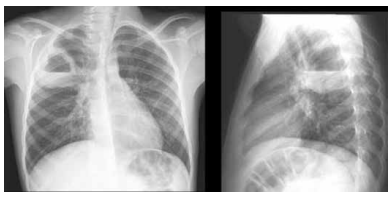

Um idoso de 76 anos de idade, em reabilitação neurológica devido a um hematoma subdural, após sofrer queda da

própria altura, em uso de gastrostomia (passada em internação prolongada recente há menos de uma semana), dirigiu-se ao

pronto-socorro, trazido pela família e proveniente de instituição de reabilitação para idosos. O paciente foi trazido devido a um

quadro de febre, à confusão mental e à dispneia já há três dias. Foi realizada radiografia de tórax na admissão, cujas imagens

estão dispostas a seguir.